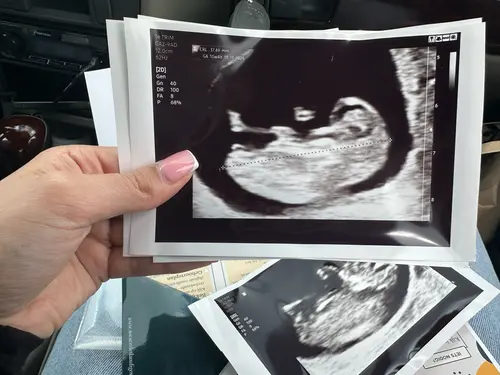

Vandaag 11 weken, echo is van gisteren. 馃┓馃┑

Wat denken jullie?馃┓馃┑

Jongetje馃挅馃┑馃┑